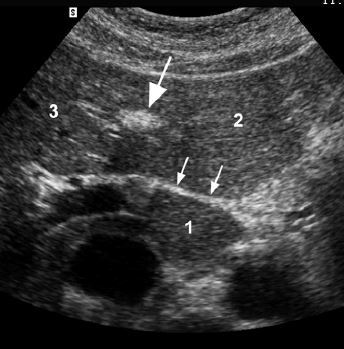

A

1. caudate lobe

2. segment II/III

3. segment IV

• large arrow - ligament teres

• small arrow - ligamentum venosum